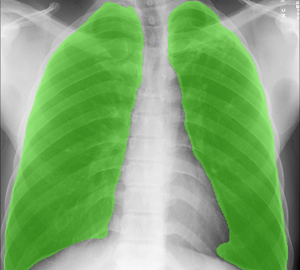

Inteligencia artificial aplicada a imágenes, ya sean de bases de datos existentes o generadas en tiempo real, hacemos implementaciones de modelos con cámaras y otros periféricos para la captura de patrones en el mundo real y la automatización de respuestas.

Para lo que no se pueda resolver con análisis matemático tradicional, podemos hacer uso de redes neuronales convolucionales y recursivas. Efectuamos el proceso de ingeniería de caracteristicas para el entrenamiento de la arquitectura de red neuronal modelada especialmente según se requiera.